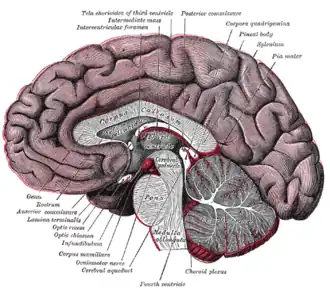

The pineal body is labeled in these images.

Mesal aspect of a brain sectioned in the median sagittal plane

Mesal aspect of a brain sectioned in the median sagittal plane -

Median sagittal section of brain

Median sagittal section of brain -